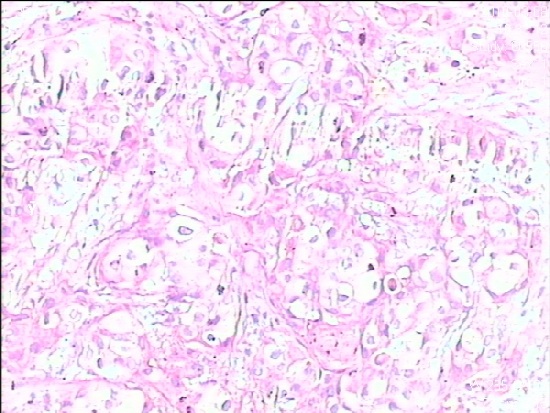

标题: X7009,病理结果:“右”乳腺浸润性导管癌,淋巴结转移癌 [打印本页]

标题: X7009,病理结果:“右”乳腺浸润性导管癌,淋巴结转移癌